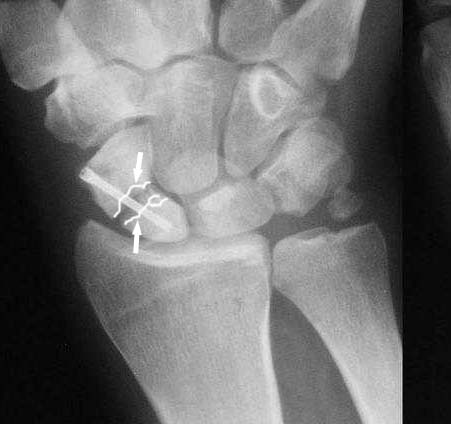

Ув. Данил! По моему мнению все-таки ложный сустав -склероз отломков (приложение), 5 мес, диастаз. Для подтверждения можно выполнить КТ кистевого сустава (формирование замыкательной пластинки, склероз концов отломков и т.д.,), а так же по КТ можно выявить сохраняется ли подвывих каких-либо костей запястья или нет. При наличии ложного сустава целесообразно будет удалить винт,обработать концы отломков, разрушив замыкательные пластинки и выполнить остеосинтез ладьевидной кости винтом с костной аутопластикой зоны псевдоартроза (либо гидроксиаппатитом...) Гипс 1,5 мес мин. Снимков найти сейчас не получилось. позже дошлю.